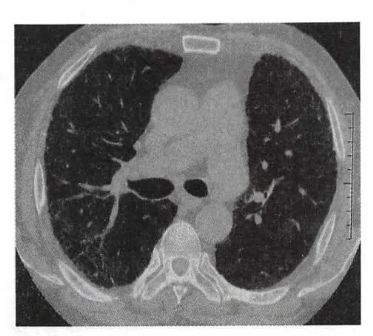

1. 胸部高分辨率CT(HRCT):可以显示UIP的特征性改变(如下图),诊断UIP的准确性大于90%,因此HRCT已成为诊断IPF的重要方法,可以替代外科肺活检。HRCT的典型UIP表现为:①病变呈网格改变,蜂窝改变伴或不伴牵拉支气管扩张;②病变以胸膜下、基底部分布为主。

特发性肺纤维化